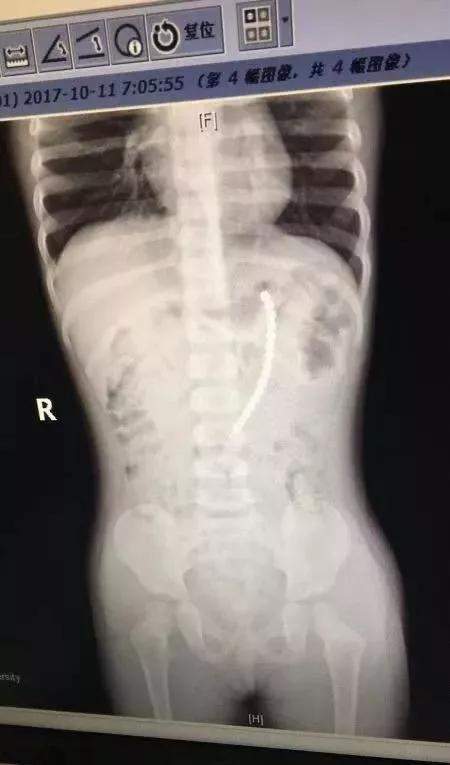

上海一个二胎家庭 , 父母给7岁的老大购买了一套巴克球 , 没想到 , 一天奶奶发现二宝正把一颗巴克球往嘴巴里放 。 奶奶吓坏了 , 急忙送医 。 通过拍片发现 , 竟然一共有19颗珠子在二宝体内!!其中一排珠子已经穿出胃壁 , 到外面去了 。 也就是说 , 孩子肠子和胃 , 都被巴克球穿孔了!万幸的是 , 这个2岁女孩吞珠后还算送医及时 。 医生取出珠子后 , 再把小女娃的胃和小肠补上 。